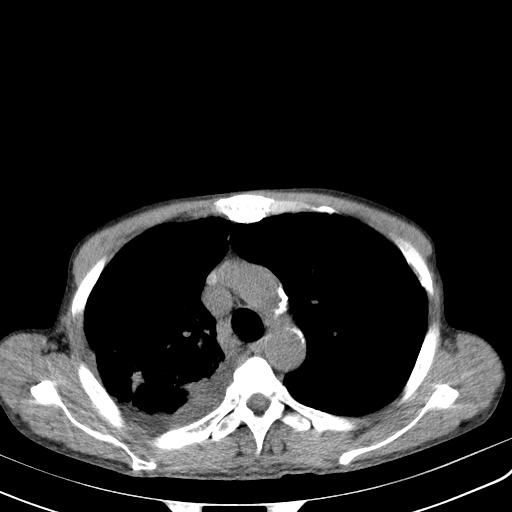

男性 75  咳嗽 一周前发热最高达39

右肺继发型tb并右侧tb性胸腔炎,右侧胸腔大量积液并右下肺膨胀不全,慢支肺气肿、多发肺大泡。建议抽胸水实验室检查并复查排除恶性在占位。

右上肺继发型肺结核,右胸腔中等量积液。

结核的基础上有纵隔淋巴结肿大,右侧有胸水,但右侧纵隔反而窄,说明有肺有不张。

再就是右下肺有块影,和不张混合,还是不能除外肺癌。

1)右肺继发型肺结核。2)左肺胸膜下多发性肺大泡。3)右侧胸腔积液。